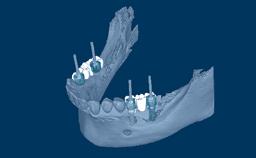

As próteses fixas implantossuportadas visam fornecer substitutos para dentes ausentes que são capazes de resistir à demandas funcionais e imitar com acurácia a estética das unidades denteais ausentes. Idealmente, a prótese deve ser indistinguível da dentição ao redor. Para atingir este objetivo, o clínico deve selecionar os melhores materiais disponíveis para enfrentar os desafios da situação clínica. Este módulo discutirá os materiais dentários disponíveis para a fabricação de próteses implantossuportadas e os princípios básicos envolvidos na seleção do material mais adequado para cada caso.